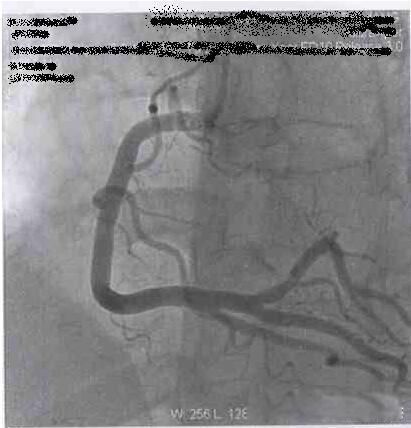

3、心脏dsa造影是什么检查?dsa检查是数字减影血管造影检查。是目前经常应用于全身血管性疾病及肿瘤的检查及治疗的一种方法。指的是血管造影的影像通过数字化处理,把不需要的组织影像删除掉,只保留血管影像,然后观察血管病变,对血管狭窄进行定位测量,为诊断及介入治疗提供了真实的立体图像,从而提供了必备条件。

心脏造影首先是在手腕进行穿刺置管(在动脉放入鞘管),鞘管一头在动脉血管里,一头暴露在外面,接着通过暴露部分将造影导管送入心脏附近后的冠状动脉开口处,通过管子将造影剂注入冠状动脉,此时就可以通过X线显影看到冠状动脉具体情况,拔出管子,检查结束。

△冠状动脉显影